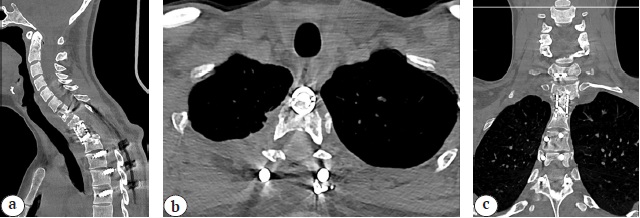

Long-term results were followed up for 12 months. In the postoperative period, the patient underwent staged courses of conservative antiparasitic therapy (albendazole) at the primary healthcare facility. The control CT indicates the absence of echinococcal process recurrence and Th1-3 block formation with the preservation of the achieved sagittal profile correction of the cervicothoracic spine (Fig. 6). The result on the ODI questionnaire was 13%. The histological examination of the surgical material verified echinococcosis.

Fig. 6. CT images 12 month post-op: no signs of hydatid disease recurrence, anterior fusion formation Th1-3 with sagittal cervico-thoracic balance correction: a — sagittal view; b — axial view; c — frontal view